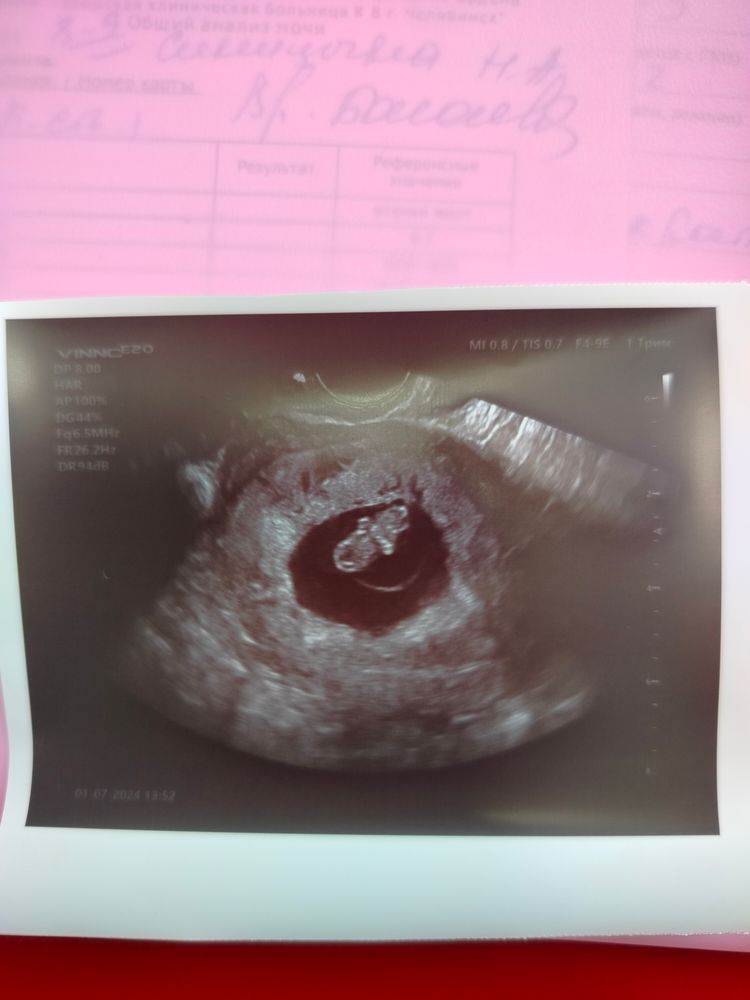

8 неделя или 34 дпп😍

Результаты УЗИРастет моя креветочка❤️❤️❤️

Поздравляю! Лёгкой беременности вам 🌹 Нам на фото 8 недель 2 дня, сейчас 9 недель . 10 на учёт. Токсикоза нет. Кушать охота каждые 2 часа🙈 . Моя любовь❤

Nadezhda, у вас прям на фото отчетливо видно кроху,а я у себя ничего не пойму😄и вам того же желаю от всей души)))растите и берегите свое сокровище❤️🙏